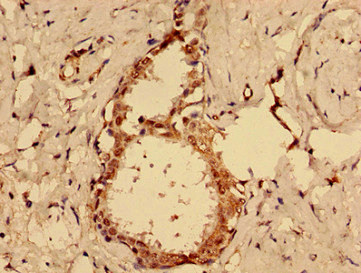

Immunohistochemistry of paraffin-embedded human ovarian cancer using CSB-PA872420LA01HU at dilution of 1:100